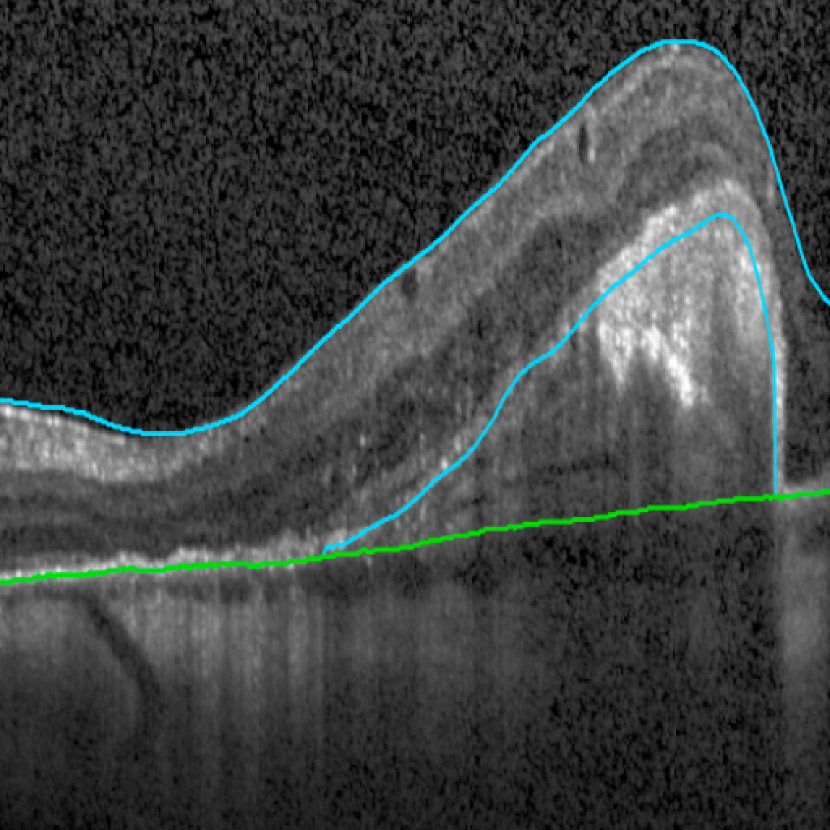

Bruch’s Membrane is an elastic smooth and thin structure, strategically located between the retina and the general circulation, having a crucial role in retinal function, aging and disease [14]. Automated segmentation of the BM is particularly important in the context of AMD as, unlike other common retinal diseases such as DR, RVO, or glaucoma, the BM is distinguishable from the outer RPE boundary. In specific, drusen in iAMD and PEDs in nAMD separate the RPE from BM, requiring the segmentation of the region in-between them. In addition, in case of GA, the RPE is completely lost in some locations, exposing only the BM, thus imposing additional difficulties for algorithms and calculations that depend on the RPE position. Achieving correct automated identification of the BM is challenging in many cases, mainly due to the small thickness of this layer, the high reflectivity of the RPE that shadows parts of the BM, and the noise being present in the scans, which is often indistinguishable from the content of drusen and PEDs (Fig. 4). Due to these difficulties, currently many automated solutions either do not provide a segmentation of the BM or its segmentation is often inaccurate in retinal OCT with AMD, leaving this clinically relevant segmentation task unaddressed or under-explored.

(a) iAMD

(b) nAMD

(c) GA